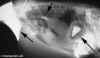

De volgende foto toont duidelijk de enorm vergrootte kliermaag, aangegeven

door de pijltjes.